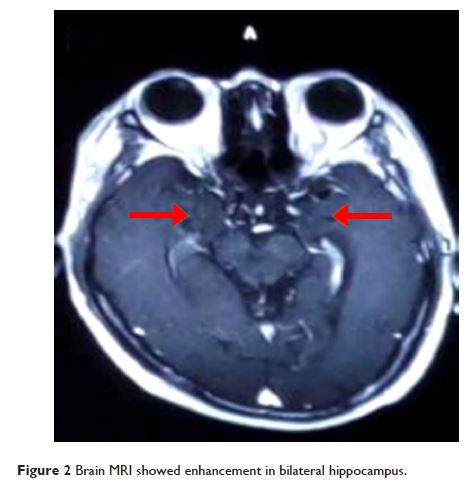

- 作者:Meiling Wang, Xiaoyu Cao, Qingxin Liu, Wenbin Ma, Xiaoqian Guo, Xuewu Liu

- 期刊:Neuropsychiatric Disease and Treatment